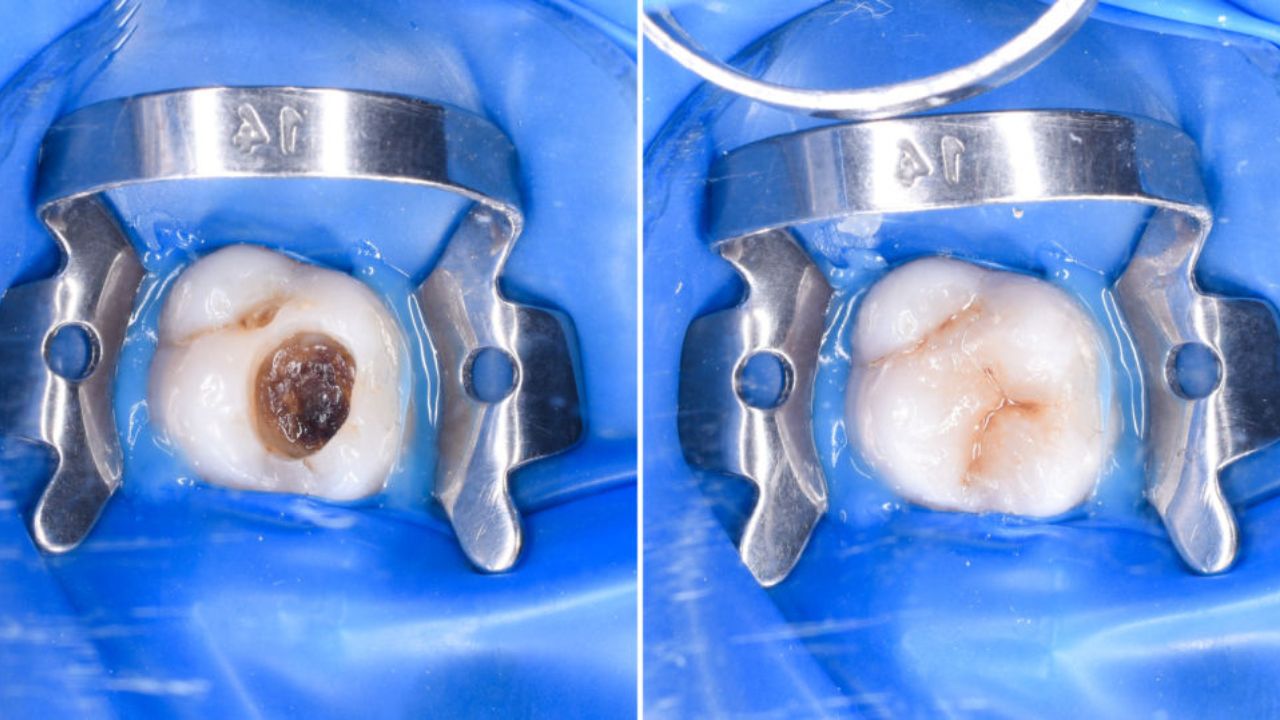

Close perfeito na coroa dental restaurada.

Contraste nítido entre o dente escurecido e o novo branco.

Antes: mancha profunda de cárie no molar.

Depois: restauração em resina com anatomia natural.